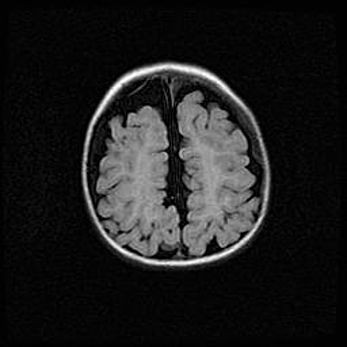

Сообщающаяся гидроцефалия. Кистозная энцефаломаляция головного мозга.

Возраст: 3 месяца 4 дня

Вес: 3100 г

Пол: женский

Окружность головы: 34 см

Срок гестации: 31 неделя

Кистозная энцефаломаляция головного мозга - одна из форм поражения головного мозга в детском возрасте. Характеризуется возникновением множественных и распространённых кист в коре, белом веществе и подкорковых образованиях головного мозга у плодов, новорождённых и детей раннего возраста. Развитие кистозной энцефаломаляции связано с внутриутробной асфиксией и гипотонией, родовой травмой, тромбозом синусов, пороками развития сосудов, инфекциями, сепсисом и другими причинами. Наиболее значимые инфекционные агенты: вирусы простого герпеса, цитомегалии, краснухи, токсоплазмы, энтеробактерии, золотистый стафилококк и другие.